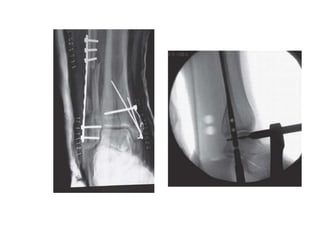

FUNCTION:

Stability- resists external rotation, axial, & lateral

displacement of talus

Weight bearing- allows for standard loading

• Diastasis requires rupture of three strong ligaments and

iterosseous membrane, hence suggesting a very substantial

insult to ankle.

• Severe abduction forces causes  torsional movement of

talus which  forces the tibia and fibula causing 

syndesmosis injury.

• Pronation type is frequently associated with syndesmosis

injury than Supination injuries.

• PER with deltoid rupture is particularly at high risk.

• Radiographic evaluation of Syndesmosis injury

• On AP view

– Tibio fibular clear space > 5mm (synd-A)

– Tibio fibular overlap <5mm (synd-B)

• On Mortise view

- Tibio fibular overlap <1mm (synd-B)

Comparison radiograph of opposite normal ankle is

more accurate.

• Intra operative stress testing:

(1)Lateral force to heel to displace the fibula

laterally (cotton’s test)

(2)Pulling the fibula laterally with a hook (hook

test) – most popular by the surgeons

(3)External rotation stress test

cotton’s test

Hook test